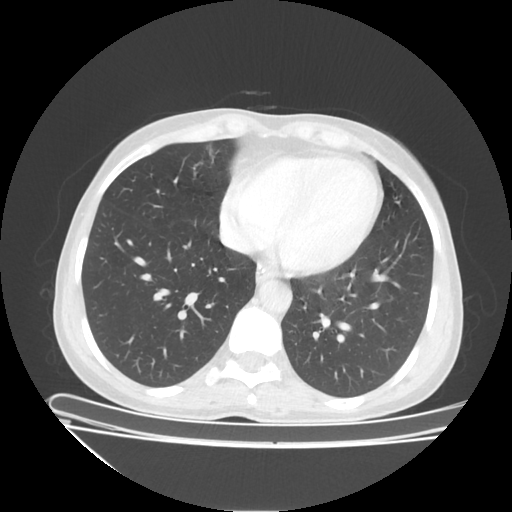

Generated VENOUS CT scan (A→B translation)

No window - Raw intensity values

Lung window (WL -600, WW 1500 β†’ Low βˆ’1350, High +150)

Mediastinum window (WL 40, WW 400 β†’ Low βˆ’160, High +240)